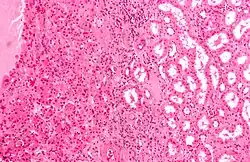

| Micrograph of a renal oncocytoma, a type of benign kidney tumour. H&E stain. | |